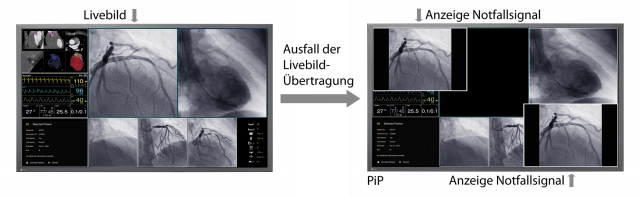

- Hohe Funktionszuverlässigkeit durch redundate Komponenten im Gerät.